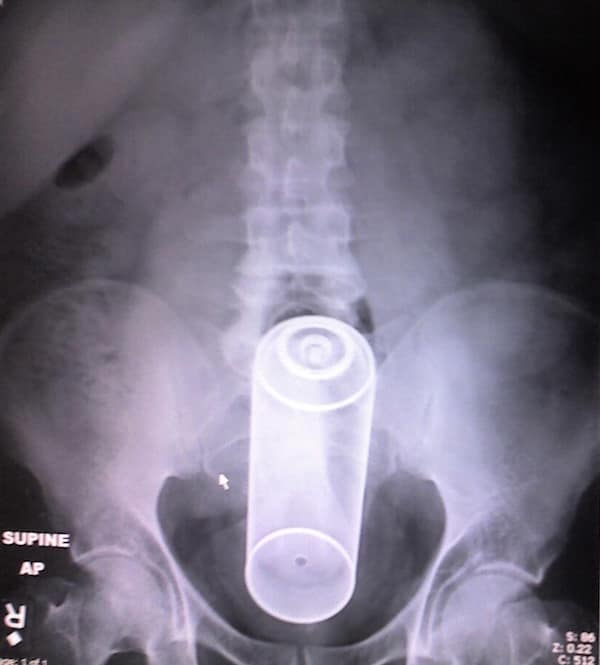

Weird xray photos

I used to think that nothing could surprise me anymore—until I stumbled upon some weird x-ray photos that made me reconsider my stance on human ingenuity (or lack thereof). Apparently, some people have a knack for getting objects lodged where they absolutely shouldn’t be. If you’ve ever wondered how not to use everyday items, these images might provide some unintended guidance.

This collection showcases 31 bizarre x-ray images that defy logic and anatomy textbooks alike. Each photo reveals unexpected objects making cameo appearances inside the human body, turning medical imaging into a gallery of the absurd. From common household items inexplicably found in unusual places to anomalies that would leave even seasoned doctors scratching their heads, these images offer a perplexing glimpse into the more “creative” side of medical emergencies. They highlight the intersection of curiosity, misadventure, and perhaps a dash of poor decision-making, all captured through the lens of radiology.